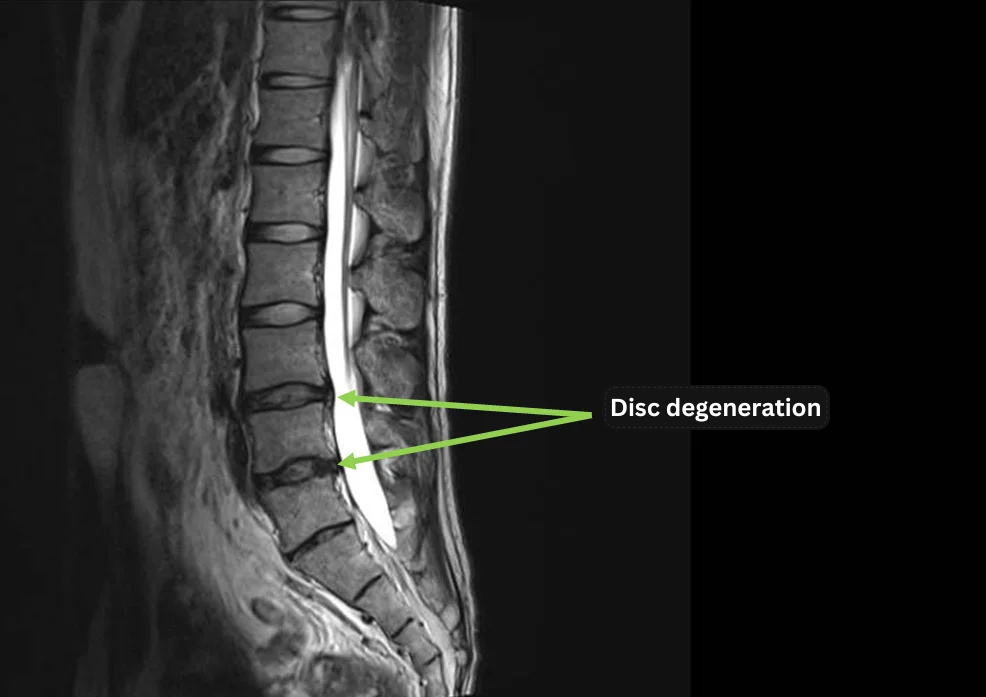

- Disc degeneration observed at L4/5 and L5/S.

- Axial imaging at L4/5 shows annulus fibrosus tear in the intervertebral disc.